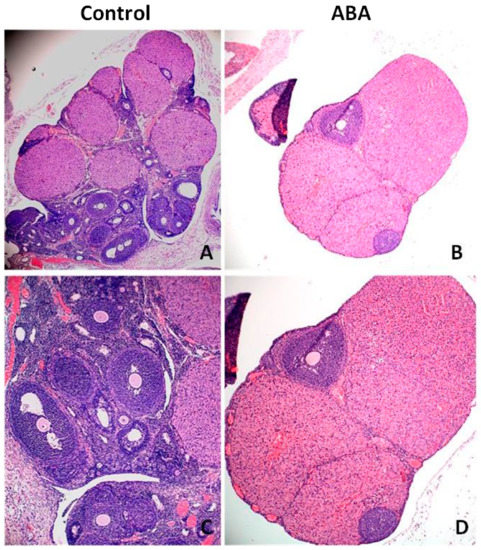

Microscopic analysis of ovarian tissue revealed a reduction in the number of antral follicles (Figure 8). The ovaries of healthy rats contained more follicles at various stages of growth, including the dominant follicle, while the ovaries from the ABA group had a poor pool of follicles without a leading follicle. The expression of Inhibin B was significantly higher in the ABA group (Figure 9).

Figure 9.

Hematoxylin–eosin-stained cross sections of rat’s ovaries with antral follicles in the control group (A,C) and ABA group (B,D). The ABA group is characterized by a poor follicle pool; only a few follicles were observed in the marginal part of ovaries. Total magnification: 40× (A,B); 100× (C,D).